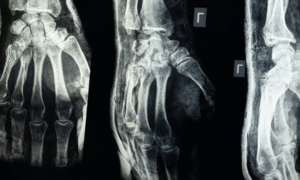

El dedo en gatillo es un padecimiento común en el ámbito laboral por actividades repetidas que suelen lesionar al aparato flexor y por consecuente generar dolor al realizar el movimiento. El tratamiento con medicamentos y desinflamatorios puede ayudar a controlar los síntoma. Cuando el dolor es persistente y el bloqueo o engatillamiento del dedo evidente el tratamiento quirúrgico es el tratamiento de elección.